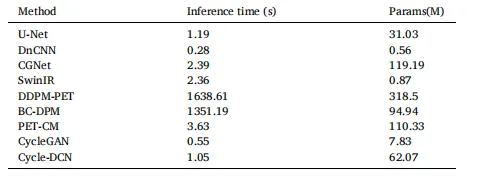

The proposed Cycle-DCN model was systematically compared with several established image denoising and restoration methods, including widely used U-Net, classic denoising model DnCNN (Zhang et al., 2017), the more recent image restoration model CGNet (Ghasemabadi et al., 2024), the Swin Transformer-based SwinIR, CycleGAN, and three diffusion-based approaches: DDPM-PET, PET-CM, and BC-DPM. Table 1provides the quantitative results, showing the mean, standard deviation, and statistical significance based on paired t-tests for each evaluation metric. Fig. 4(a) presents a visual comparison of a representative slice across the nine models, along with the corresponding full-dose and low-dose images at three different dose levels.For ¼ low-dose images, the PSNR, SSIM, and NRMSE metrics are comparable across all evaluated models. While DnCNN and SwinIR slightly outperforms Cycle-DCN in some measures, these differences are not statistically significant (p > 0.05). In contrast, for the more challenging 1/24 low-dose images, Cycle-DCN achieves superior metric values. The three diffusion-based methods—DDPM-PET, PET-CM, and BC-DPM—consistently yielded inferior performance under all the three low-dose conditions. As shown in Fig. 4(a), U-Net and DnCNN result in excessive smoothing, leading to increased deviation from the full-dose images at lower dose levels, with small sulci becoming nearly indistinguishable. However, Cycle-DCN remains closer to the full-dose images, demonstrating better robustness. In the enlarged views in Fig. 4(b), Cycle-DCN uniquely preserves brain structures such as sulci and gyri, producing visual outputs more consistent with full-dose images compared to other models. Among the three diffusion-based methods, DDPM-PET produced visually promising results across all dose levels. However, the performance of BC-DPM (trained unconditionally) and PET-CM (with two-step sampling) deteriorated rapidly as the dose decreased, resulting in significantly degraded image quality.

4.1 定量评估 4.1.1 峰值信噪比(PSNR)、结构相似性指数(SSIM)及归一化均方根误差(NRMSE)对比 将所提Cycle-DCN模型与多种已有的图像去噪和恢复方法进行了系统对比,包括广泛使用的U-Net、经典去噪模型DnCNN(Zhang等,2017)、较新的图像恢复模型CGNet(Ghasemabadi等,2024)、基于Swin Transformer的SwinIR、CycleGAN,以及三种基于扩散的方法(DDPM-PET、PET-CM和BC-DPM)。表1给出了定量结果,包括各评估指标的均值、标准差以及基于配对t检验的统计显著性。图4(a)展示了九种模型在三个不同剂量水平下,代表性切片的视觉对比,同时呈现了对应的全剂量和低剂量图像。 对于¼低剂量图像,所有评估模型的PSNR、SSIM和NRMSE指标表现相当。尽管DnCNN和SwinIR在部分指标上略优于Cycle-DCN,但这些差异无统计学意义(p > 0.05)。相比之下,在更具挑战性的1/24低剂量图像中,Cycle-DCN取得了更优的指标值。三种基于扩散的方法(DDPM-PET、PET-CM和BC-DPM)在所有三个低剂量条件下均表现出持续劣势。如图4(a)所示,U-Net和DnCNN存在过度平滑问题,导致在低剂量水平下与全剂量图像的偏差增大,细小脑沟几乎无法区分。而Cycle-DCN始终更接近全剂量图像,展现出更强的鲁棒性。在图4(b)的放大视图中,Cycle-DCN独特地保留了脑沟、脑回等脑部结构,生成的视觉结果比其他模型更接近全剂量图像。在三种基于扩散的方法中,DDPM-PET在所有剂量水平下均产生了视觉上较理想的结果,但无监督训练的BC-DPM和两步采样的PET-CM的性能随剂量降低迅速下降,导致图像质量显著退化。

Table 4 Inference Time and Parameters of Different Models

表4 不同模型的推理时间与参数对比